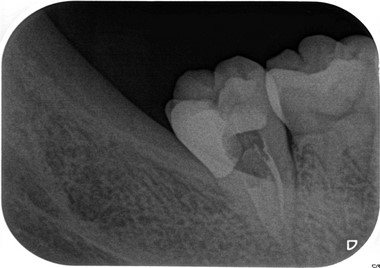

【症例】智歯による第2大臼歯遠心カリエス

(EEデンタルブログより引用)

?毎度おなじみのエアースケーラー用チップを使用してチマチマ削ります。

(カボ・ナカニシのダイヤル調整型を使い、パワー設定は基本2で使用してください)